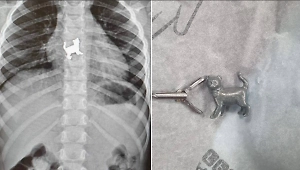

Врачи Подольской областной клинической больницы спасли 64-летнего мужчину, который пожаловался на боли в пищеводе. Оказалось, что во время еды у него открепился металлический зубной мост и пациент его проглотил.

"При визуальном обследовании верхних отделов желудочно-кишечного тракта повреждений слизистой пищевода не было выявлено, а при осмотре желудка был обнаружен проглоченный металлический зубной мост. Мы извлекли зубной протез с помощью специальной петли. С момента обращения пациента до извлечения инородного тела прошло около 30 минут", — сообщил врач-эндоскопист отделения эндоскопии Подольской больницы Виктор Чернов.

Подольские врачи спасли пациента, проглотившего зубной мост. Фото © Минздрав Московской области